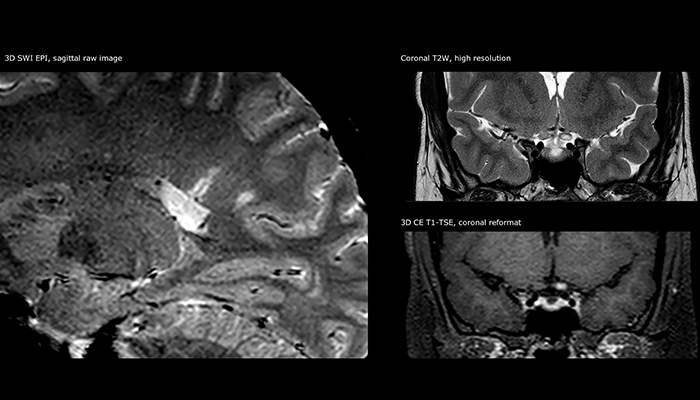

“Ingenia 3.0T provides us very good image quality with high SNR, even if we push the resolution. For example, in FLAIR images we may have an isotropic resolution of 0.9 mm. Ingenia allows us to use 3D T1 TSE with BrainView, which has a better sensitivity than 2D spin echo imaging[2] and 3D gradient echo imaging. Ingenia also provides highly reproducible exams, which is important in MS imaging so that follow-up exams at different time points are done the same way.”

Imaging MS in brain

For MS imaging in the brain, Dr. Savatovsky uses 3D FLAIR as the basic sequence to visualize the lesions and assess the situation and lesion load. “We count the lesions in each location to determine if the criteria of the disease are fulfilled. We use a T2-weighted sequence because our neurologists are used to it. We compare the lesion load on FLAIR with a 3D T1 post-contrast sequence to help us determine whether lesions are old or new. We typically administer the contrast before the patient enters the machine because it shortens the examination time and allows to visualize active lesions that tend to be more visible after several minutes. When a differential diagnosis is difficult, we add sequences such as susceptibility imaging, because some focal MS lesions have a small vein in the center[3].”